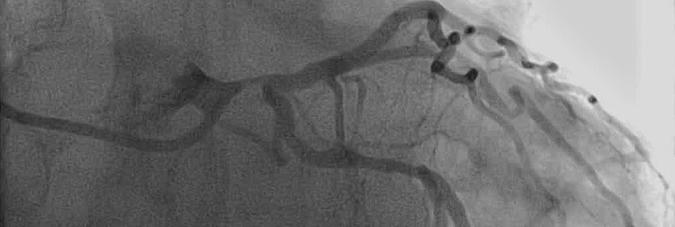

The optimal method of revascularization for patients with left main coronary artery disease (LMCAD) is controversial. Coronary artery bypass graft surgery (CABG) has traditionally been considered the gold standard therapy, and recent randomized trials comparing CABG with percutaneous coronary intervention (PCI) with drug-eluting stents (DES) have reported conflicting outcomes.

Isolated left main stenosis in a young patient with low syntax score